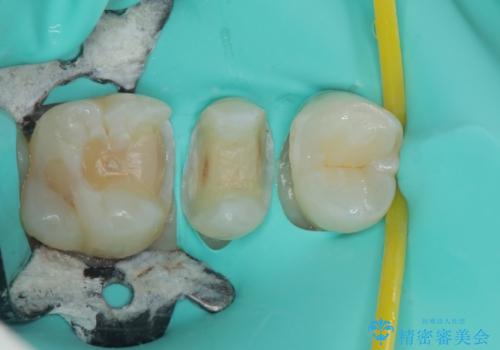

拡大鏡視野下で銀歯、虫歯の除去を行い、ハイブリッドインレーに適した形に整えました。

歯と歯茎の間に圧排糸と言われる糸を入れてシリコーン印象材にて精密な型どりをしました。

ハイブリッドインレーの装着時には、唾液の侵入を防ぐために、ラバーダム防湿を行いました。